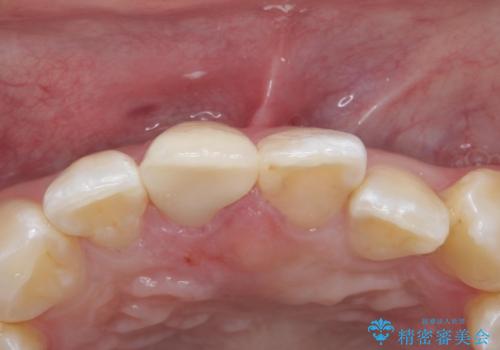

色・形ともに改善され、大変喜んでいただけました。